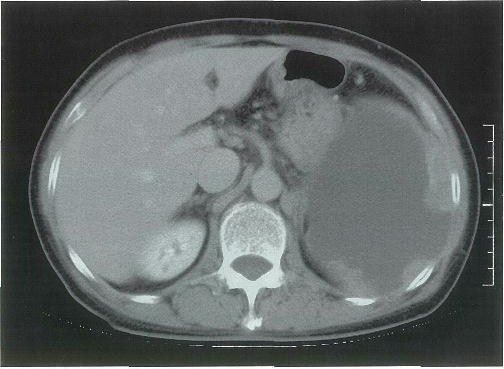

71歳の男性。呼吸困難を主訴に来院した。20歳から40年間,ビル建設の仕事に従事した。喫煙 20本/日を30年間。胸水中のヒアルロン酸は92300ng/mlと著明な増加を示す。胸部エックス線写真と胸腹部造影CTとを別に示す。

診断 悪性胸膜中皮腫